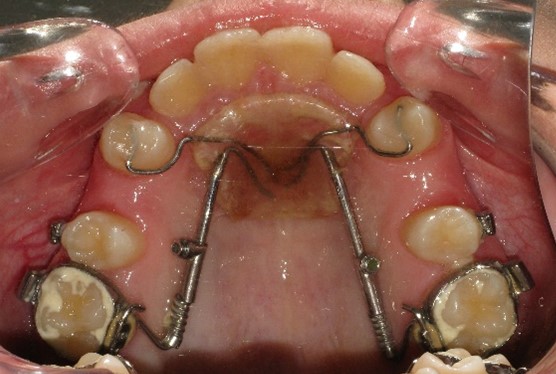

В плане ортодонтического лечения необходимо провести дистализацию боковых сегментов на верхней челюсти с постановкой моляров по нейтральному типу с последующей нормализацией формы зубных рядов на обеих челюстях и окклюзии. Первый этап лечения проводится с помощью несъемного дистализирующего аппарата – Distal Jet. (рис.4)

Данная конструкция ортодонтического аппарата выбрана обьективно, учитывая возраст пациента и незрелость костной ткани альвеолярного отростка на данном этапе формирования прикуса постоянных зубов. В более позднем возрасте целесообразно применение ортодонтических миниимплантатов с целью анкоража для дистализации боковых сегментов на верхней челюсти с постановкой моляров по нейтральному типу. Период дистализации первых моляров верхней челюсти с помощью аппарата Distal Jet занял примерно 5 мес. Отмечается корпусное перемещение моляров без изменения их осевого наклона в сагиттальном направлении, что дают конструктивные особенности аппарата Distal Jet с соответствующей силовой нагрузкой пружины NiTi . (рис.5)

Рис.4. Аппарат Distal Jet в полости рта на начальном этапе дистализации.